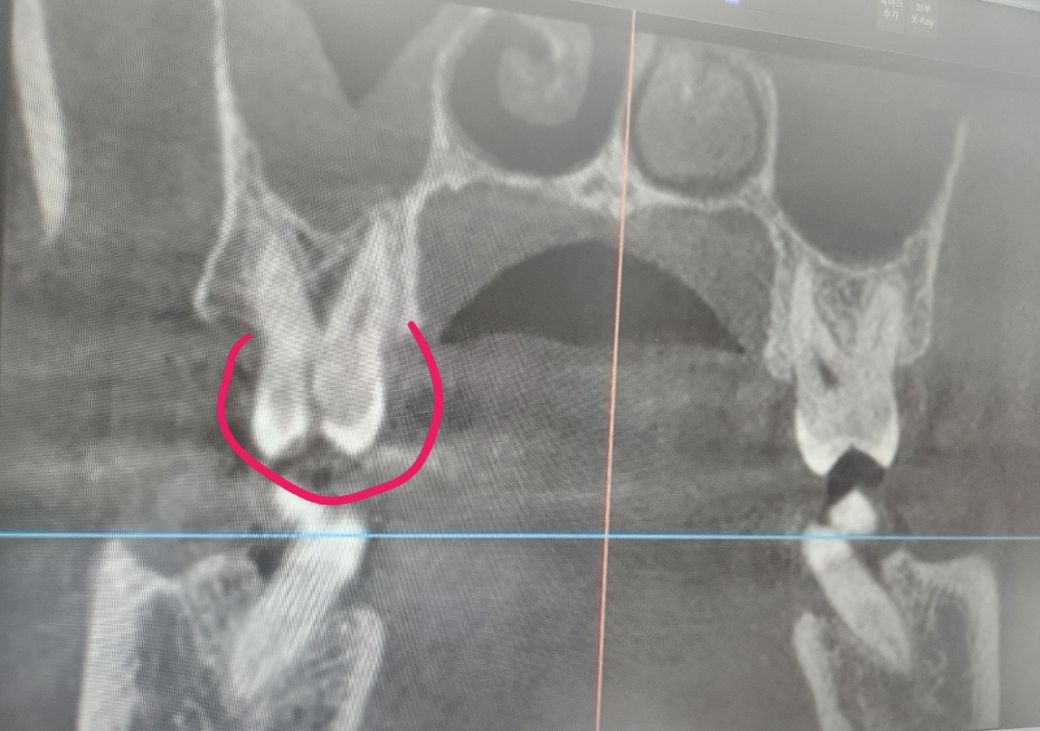

오른쪽 윗 어금니 치아 금(파절) 치료 방법 문의드립니다

수고하십니다! 2년전부터 오른쪽 윗 어금니쪽이 씹을때마다 통증과 찬물 시림 등 통증이 있었는데 최근 들어 통증이 심해지고 심지어 자고 있을때도 갑자기 극심한 통증이 있어서 너무 힘들었네요 치과를 내원해본 결과 CT와 사진상으로 보여지듯이 치아 파절이 있다고 합니다 발치해서 임플란트로 하는 수밖에 없다고 말을 들었는데요 혹시 신경치료나 크라운 등 다른 방법 없이 바로 임플란트로 결국 가야될까요? 바쁘시겠지만 답변해주시면 치과진료에 도움이 많이 될껏같습니다 감사합니다!

x-ray 사진으로 보아 치아가 정중앙으로 파절되고 치아뿌리끝에 염증도 있어 보입니다. 이런경우 신경치료해도 효과가 없는 경우가 대부분입니다. 발치할 수 밖에 없을 것으로 보입니다.

사진상으로나 엑스레이 상으로 치아가 완전히 반파 난거 같습니다 .치료를 하기에는 너무 늦엇고 발치를 하셔야될것같습니다.

치아 파절의 정도가 심하기 때문에 같은 상황이라면 발치를 우선적으로 고려할 것 같습니다.

크랙 치아의 경우 치료가 쉽지 않습니다. 현 증상으로 봐서는 일단 신경치료를 해볼 순 있으나 하더라도 온전히 증상이 사라지지 않을 가능성도 있습니다.